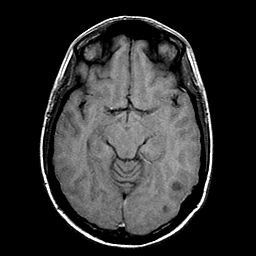

Sarcoma, MR Study #1 mr-t1 -- Slice #9

[Home][Help][Clinical] Slice 9